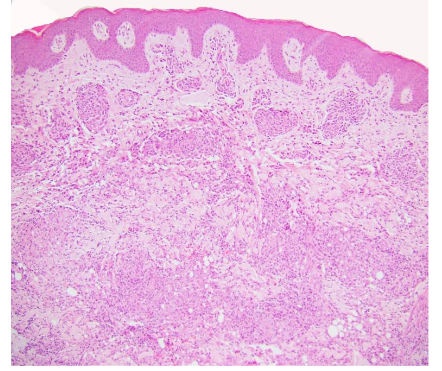

Psoriasis is the most common dermatologic condition in patients with IBD, more common in CD than UC, affecting 7-11% of patients. Psoriasis patients have a high risk of developing IBD. Genome wide studies have identified 11 genes of predisposition common in psoriasis and CD. First degree relatives of patients with CD will have psoriasis in 10% vs 3% of controls. The onset precedes IBD, and the course is independent of activity. Anti-TNF therapy may be a trigger for psoriasis. In fact, immune-related adverse events (IrAEs) may be seen in up to 22% of patients being treated with anti-TNF, a biologic used for the treatment of IBD, with eczematous or psoriasiform eruptions included. Clinically, patients with psoriasis present most commonly with the chronic plaque type which is characterized by well-circumscribed erythematous plaques covered with silvery scales. Histologically, fully developed lesions are characterized by regular acanthosis of the rete ridges with bulbous or “clubbing” tips sometimes with fusion, mitotic figures may be present 1-2 layers above the basal layer, and tortuous capillaries are present in edematous elongated dermal papillae with overlying thinning of suprapapillary epidermal plates. In addition, there is hyperkeratosis with confluent horizontal parakeratosis and hypogranulosis of the underlying superficial epidermis. 75% of cases have collections of neutrophils within the parakeratotic areas, known as Monro microabscesses and less commonly within the spinous layer, known as spongiform pustules of Kogoj. The dermis shows a superficial perivascular lymphocytic infiltrate with rare neutrophils.